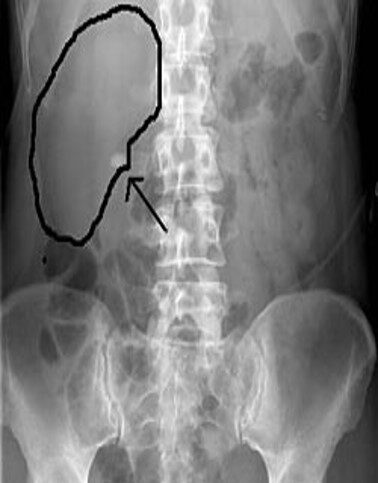

یافته های تشخیصی:

تشخیص نهایی با:

رادیولوژیک